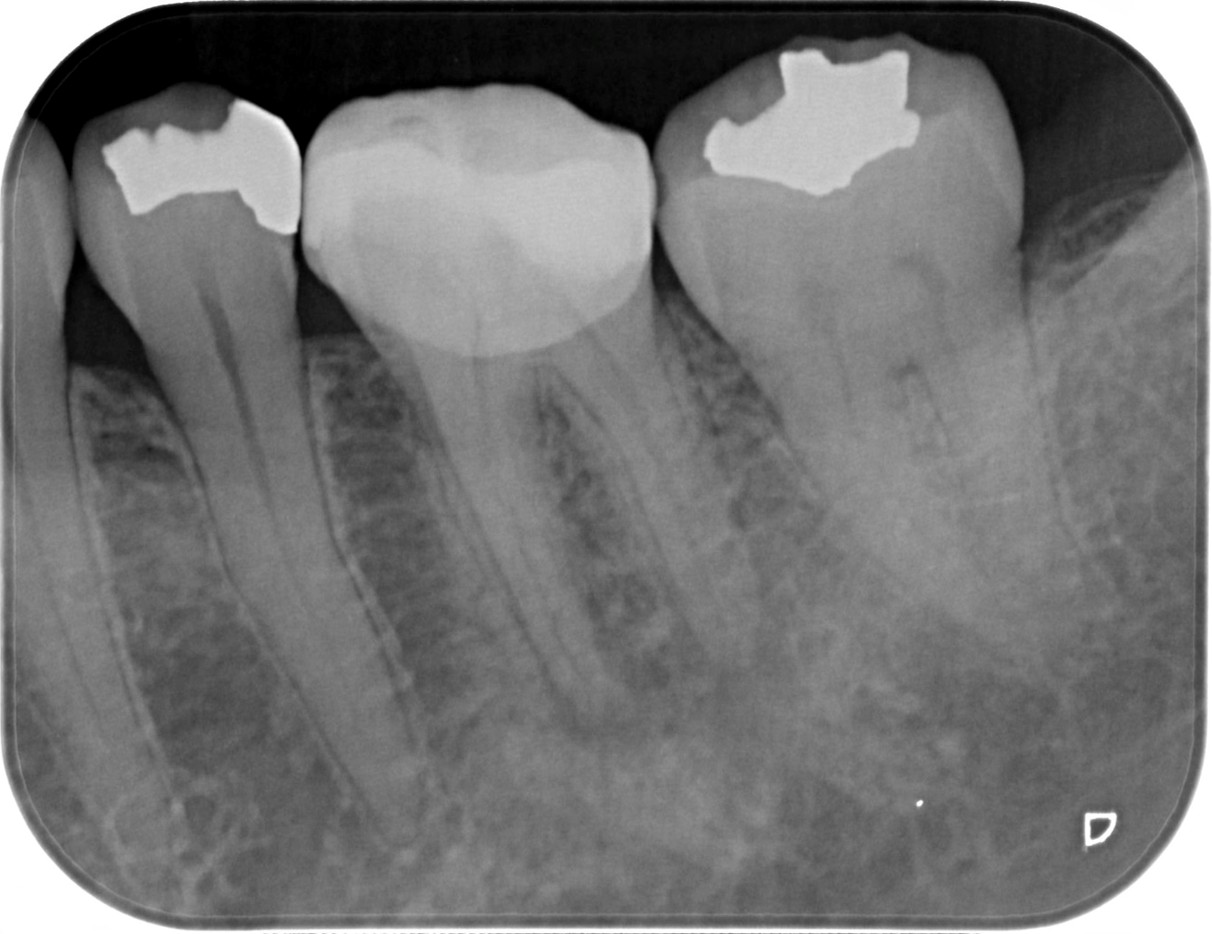

症例4

治療経過

①![]() 術前 |

②![]() 根管治療後3か月経過 |

③![]() 根管治療後1年経過時 |

④![]() 根管治療後2年経過時 |

神経の治療後、①→②→③→④と時間をかけて徐々に治ってくることがあります。

神経の治療は細菌感染を除去する治療です。細菌がいなくなれば、無駄に神経をとらなくても良い歯もあるかもしれません。

| 項目 | 詳細 |

|---|---|

| 患者様データ | 30代 男性 |

| 来院時の主訴 | 「他院で右上の歯3本とも神経をとる必要があると言われた。なんとか神経を残したい。」 |

| 術前検査結果 |

右上第一小臼歯:打診痛(+)・歯髄の生活反応有り 右上第二小臼歯:打診痛(+)・歯髄の生活反応無し 右上第二大臼歯:打診痛(ー)・歯髄の生活反応有り |

| 医院の診断 |

右上第一小臼歯:健全→術前に神経が残せる可能性のある歯と診断 右上第二小臼歯:慢性根尖性歯周炎→術前に神経が残せない歯と診断 右上第二大臼歯:無症候性可逆性歯髄炎→術前に神経が残せる可能性のある歯と診断し、術中に神経を残せると診断 |

| 通院期間 | 2年半 |

| 来院回数 | 10回(定期的なチェック含む) |

| 治療費 | 350,000円(税抜) 《内訳》 右上第二小臼歯:精密根管治療70,000円、ファイバーポストコア20,000円、セラミック治療120,000円 右上第二大臼歯:歯髄温存療法55,000円、セラミック治療85,000円 |

| リスクと副作用 | ①根管治療歯は長期的には破折するリスク ②メインテナンスが必要 |

| ココがこだわりのポイント☝ |

レントゲン検査や患者様の訴える症状だけでは神経を残せるかどうかは断定できません。 この方もレントゲン写真上では神経を残せないように見える歯でしたが、治療前に検査を入念に行うことで残せる可能性を見出すことができました。 同じ悩みを抱えた方は是非お気軽にご相談下さい。 |